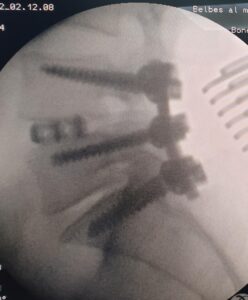

قام الفريق الطبي بقسم جراحة المخ والأعصاب بمستشفي بلبيس المركزي بقيادة الدكتور أحمد شلبي استشاري جراحة المخ والأعصاب، والدكتور تميم عيسوي رئيس القسم، والدكتور سامح سلامة أخصائي جراحة المخ والأعصاب، والدكتور أحمد عادل أخصائي التخدير، وبإشراف مدير المستشفى، بإجراء أول جراحة في تخصص جراحة المخ والأعصاب ذات مهارة فائقة، بقرار علاج نفقة الدولة، دون تحمل المريض أي أعباء مالية، حيث تم تثبيت الفقرات القطنية الرابعة والخامسة والأولي العجزية، لحالة تعاني من انزلاق غضروفي قطني مرتجع، وتم استئصال الغضروف وتركيب قفص كربوني، وتثبيت الفقرات بواسطة مسامير وأعمدة، تحت مخدر عام بالعمليات، والمريض الآن بحالة جيدة ومستقرة.